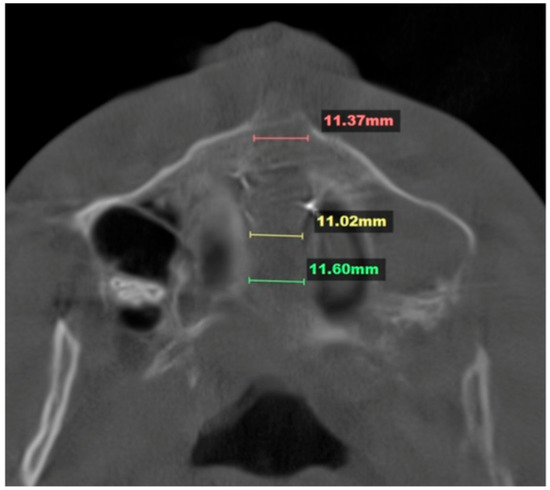

Background/Objectives: Mini-Screw-Assisted Rapid Skeletal Expansion (MARPE) appliances have been widely used for maxillary skeletal expansion in non-growing subjects and adolescents with a fused midpalatal suture. The current case report describes the immediate 3D cephalometric changes in the skeletal and soft tissue parameters, [...] Read more.

Background/Objectives: Mini-Screw-Assisted Rapid Skeletal Expansion (MARPE) appliances have been widely used for maxillary skeletal expansion in non-growing subjects and adolescents with a fused midpalatal suture. The current case report describes the immediate 3D cephalometric changes in the skeletal and soft tissue parameters, along with upper airway volume, shape, and dimensions, in a patient with Skeletal Class I anterior underbite. Methods: The pre- and post-expansion full-face Cone-Beam Computed Tomograms (CBCTs) of a 19-year-old patient who underwent 3D-guided midpalatal piezocorticotomy-assisted MARPE were compared and analyzed using 3D cephalometric software. Both CBCT volumes were re-oriented relative to the Frankfurt horizontal plane (FHP) to accommodate postural changes. Results: The total upper airway volume and minimum upper airway cross-section increased after expansion. The nasal base plane (ANS–PNS) rotated in all three spatial planes, including the sagittal plane (anterior downward and posterior upward rotation, with the center of rotation around the maxillary center of rotation) and the vertical plane (upward rotation on the left side). The maxillary canine and molar cant planes rotated around the center of rotation in the midface, with left upward and right downward rotation. The orientation of the ANS–PNS plane changed due to the leftward rotation of the ANS, with the center of rotation approaching the PNS. Cervical curvature improved from kyphotic to lordotic immediately following expansion. Conclusions: Three-dimensionally guided midpalatal piezocorticotomy-assisted MARPE has been shown to produce midfacial changes in all three spatial planes when evaluated via 3D cephalometric analysis. Comprehensive observational studies are necessary to analyze these changes and their effects for different skeletal classifications. Full article